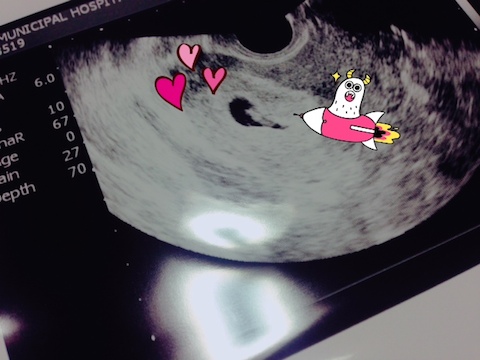

お腹の中の赤ちゃんの心拍を確認することができました^^

黒い袋の中におりました❤

経膣エコーで、小さいけど心拍がドクドクしている様子をジョーさんも一緒に見させてもらって、

そのときはさすがにジョーさんも「おー!!」と感動した様子で、

わたしも泣いてしまいました。ギャン泣きのほうじゃなくて。。。

心拍確認できることはやはり医療の世界ではとっても意味の大きいことのようで、

前回まではあんなに終始深刻な顔でリスクを説明していた先生が今回はめっちゃ軽やかになっていました。

実は今も成長が週数のわりに遅いということに変わりはなく、